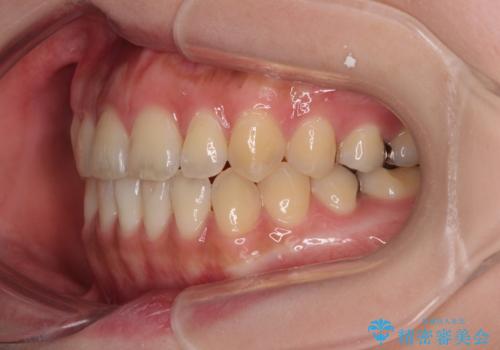

開咬をワイヤー装置で矯正治療

- 上下前歯が非接触となっている咬み合わせを気にして来院された患者様です。

開咬となっている原因の大半は、舌の突出癖によるものであるため、治療開始前から舌のトレーニングを開始し、スムーズに治療が進むようにしました。

開咬の方は、インビザライン矯正治療が適していますが、自己管理の煩わしさと、転勤の可能性がありマウスピース矯正であると通院しなくなるだろうとのことで、ワイヤー装置にて矯正治療を行うこととしました。

治療開始から8ヶ月ほどで遠方への転勤が決まりましたが、歯列は概ね整っていたため、その後は東京出張を狙って治療を終える処置を行うことができました。